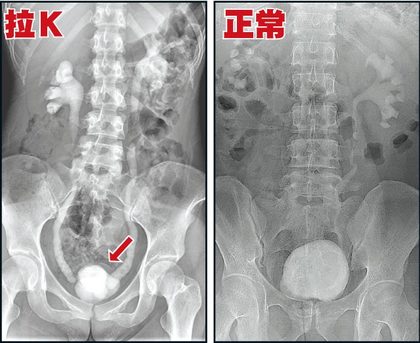

「遇見我之前 ,她包尿布不敢出門 ,但不包尿布無法出門。」日前有男網友在《DCard》發文,表示他擁有一名要包尿布的女友。原來,他的女友曾拉K,導致膀胱容量只有正常人的5分之1。女友每10分鐘就要去尿尿,有時候忍不住甚至會漏出來,讓她無法正常上班上課。